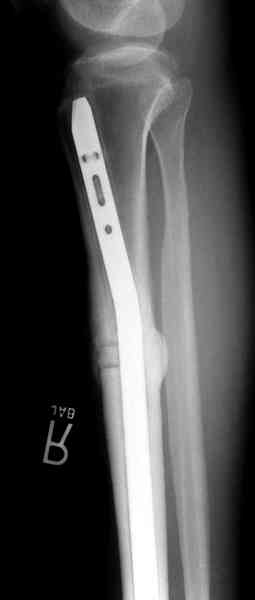

Нет. Просвет внутри кейджа - 13 мм, штифт - 12 мм. Не так там и много пространства то есть. Но вопрос правильный, интересный, из разряда современных нерешенных проблем.

По локализации и по характреру опухоли мало напоминает остеобластому, может, представленные биопсийные материалы адамантиномы помогут вашим морфологам дифференцировать опухоль (Basiloid cells, pseudoglandular pattern and peripheral palisading)

Недавно на нашей ежемесячной Morbidity&Mortality

conference мы разбирали похожий случай, ложный сустав большеберцовой кости после резекции опухоли.

К нашему онкологу-ортопеду обратился больной с жалобами на боли в голени, из рассказа - год назад была сделана биопсия большеберцовой кости, но название заболевания "не запомнил”.

Оперирован в военном госпитале с заменой сегмента

аллокостью большеберцовой кости и после демобилизации явился для постоянного наблюдения по месту жительства.

Наши имели проблему со сращением, пришлось им сделать динамизацию, дополнительную аутопластику.

Снимки представлены.

Не оригинальное, подход не раз был демонстрирован нас в стране проф. Анатолием Федоровичем Лазаревым (ЦИТО), который это называет "металлокаркасная пластика". У нас в институте в другом отделении он

помогал сделать несколько таких металлокаркасов, только, насколько я помню, без блокируемых стержней. А в мире эта методика довольно давно

применяется, хотя и не массово. Например, осенью прошлого года на конференции общества Кюнчера в Страсбурге было хорошее сообщение на эту тему. 17 больных, результаты уже до 5 лет.

The cages are commercially available but up to 10 cm. So we measured the needed length on x-rays, added 2 cm at both ends for sure that

the resected piece will include all, and resulted with 15 cm which one was ordered and individually made by the same factory. So yes, we made the gap to fit the cage.

The inner diameter of the tube is 13 mm, the nail was 12 mm, so not so much space to put something inside. Yes, this is really shaft endoprosthesis which i hardly ever would offer for a young football player. Though... Maybe we would when we collect some experience with this sort of implants to feel/prognose its strength in different settings.